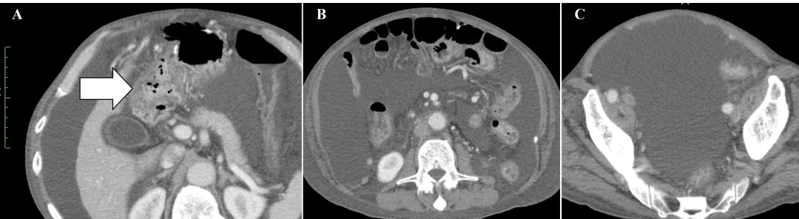

小细胞未分化宫颈癌进展快、易耐药,预后极差。《Cureus》报道了一则突破性案例:一位 50 多岁的患者术后出现肝、淋巴结多处转移,化疗失败后,采用 WT1-DC 疫苗联合放疗: 1、第 67 天(注射第 5 剂疫苗后),CT 显示肝转移灶完全消失; 2、免疫指标(中性粒细胞 / 淋巴细胞比值等)恢复正常,原本因化疗受损的免疫功能显著改善。 案例3:胰腺癌患者中位生存期突破3年,7人成功手术 胰腺导管腺癌被称为 “癌王”,对放化疗天然耐药。《癌症免疫治疗杂志》的一项研究带来了新希望:10 例不可切除的胰腺导管腺癌患者(6 例 III 期局部晚期、3 例 IV 期转移性、1 例术后复发)采用 WT1-DC 疫苗联合化疗后: 1、所有患者肿瘤负荷下降,7人达到部分缓解,3人长期稳定; 2、9例患者中位无进展生存期 2.23 年,中位总生存期更是突破 3.52 年,远超传统治疗的预期。 3、 7 例成功接受了转化手术,其中 6 例实现 R0 切除(肿瘤完全切除,无残留),1 例为 R1 切除(镜下有残留)。 案例4:晚期十二指肠癌 4.3 年无进展,恶性腹水消失 十二指肠癌占胃肠道癌症的 0.3%-0.5%,虽发病率低但侵袭性强,易快速扩散,根治性手术是唯一可能治愈的手段,但晚期患者往往失去手术机会,且针对恶性腹水缺乏有效治疗方案。 《Cureus》曾报道一则案例:一位 72 岁的晚期十二指肠癌患者,腹膜播散伴恶性腹水,化疗失败后接受 WT1/MUC1-DC 疫苗联合细胞疗法: 1、第 8 次治疗后,恶性腹水消失,腹胀、水肿等症状消退; 2、原发病灶和转移淋巴结缩小,截至报道时,肿瘤 52 个月未进展,患者未出现严重副作用,且能正常活动。 锐赛EP-DC(医迪泰)是一种通用型的DC细胞疫苗,可靶向激活免疫系统对22种常见肿瘤抗原的免疫反应。产生强大免疫应答(CD4+/CD8+)识别所有肿瘤抗原,并覆盖广泛HLA类型。 当向患者给药时,医迪泰诱导的免疫应答有可能识别及破坏体内的癌细胞并向免疫系统持续提供支持和记忆,以便其能够持续靶向及预防癌症复发的可能。 2025年初,顶尖期刊Small Science(IF 12.7)发表了yl6809永利官网首席科学家范小勇教授与复旦大学附属上海市公共卫生临床中心研究组、南方科技大学附属深圳市第三人民医院/国家感染性疾病临床医学研究中心研究组的合作研究,题为“Dendritic Cell Vaccine Harboring Inactivated Mycobacteria Induces Immune Protection Against Tuberculosis in Murine Models and is Well Tolerated in Humans”。 本研究在上海市重大传染病和生物安全研究院官网的报道 该项临床研究使用了锐赛自主知识产权的新一代EP-DC疫苗技术。此前,这一创新技术已在多项抗肿瘤、抗HPV病毒治疗的临床研究中被证明有效。本次研究是EP-DC技术在结核病临床研究的重磅亮相。 yl6809永利官网负责制备DC 范小勇教授团队的突破性研究,首次证实DC细胞应用有望成为预防和治疗结核病的新策略。同时也揭示了新一代EP-DC疫苗技术可以在感染疾病的全病程治疗中发挥重大作用。 随着论文的发表,说明锐赛新一代EP-DC疫苗技术的应用场景已从肿瘤治疗的最后防线,扩展至疾病预防、病原微生物清除、病理进展逆转、疾病辅助治疗和术后防复发的全流程。